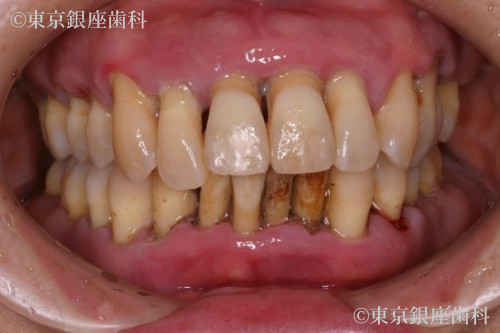

歯の揺れを原因に一度来院したが金銭的理由により一時保留。3年後歯周病が悪化し歯の揺れ、骨の吸収が見られ前歯が自然脱落し改善したい。

何年間も歯科医院には通っておらず、全ての歯の揺れがひどく今にも抜けそうだったが金銭的な理由により一時保留にしていた。3年後に来院した際には、歯周病が悪化し著しい歯の揺れ、骨の吸収が見られた。そして左上の前歯が自然脱落した。

歯周病の進行により歯に動揺があり長期の保存が難しくこのままでは予後が不安であった為全顎的な治療が必要と判断。上下全ての歯を抜歯。重度の歯周病により骨が吸収されているため、上顎骨が薄く左側は上顎洞に骨を足す治療(サイナスリフト)を行い上顎に4本、下顎に4本のインプラントを埋入しワンデイインプラントを行った。現在半年メンテナンス。